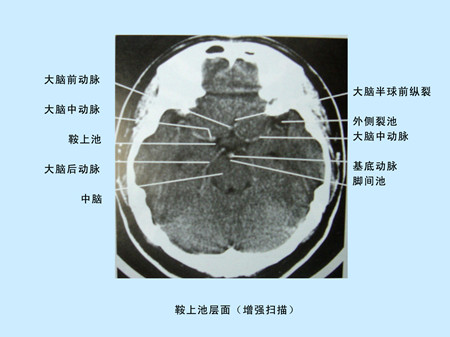

CT平掃及增強掃描腦組織圖像顯示 超聲經顱多普勒檢測時顯示圖像